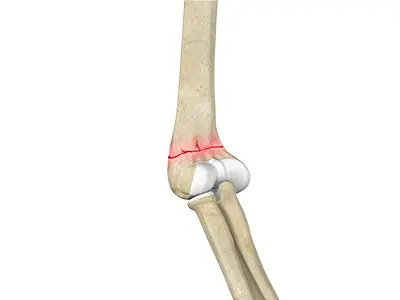

Distal Humerus Fractures of the Elbow

Injury in the distal humerus can cause impairment in the function of the elbow joint.